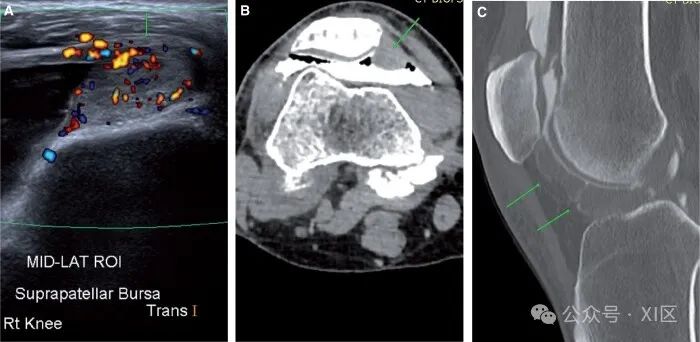

滑膜肿瘤在CT关节造影上明显可见。其中最常见的是树状脂肪瘤、色素沉着绒毛结节性滑膜炎(PVNS)和滑膜软骨瘤病。脂肪瘤树状结构在临床上表现为不消退的关节积液,有反复穿刺史。计划前CT显示髌上滑膜中存在肉眼可见的脂肪(图12A和B)。动态超声图像显示滑膜隐窝内悬挂的回声性病变。手术台上评估产生浆液性穿刺,造影后图像显示对比物包围的脂肪密度。由于正常膝关节在髌上隐窝内有脂肪,脂肪瘤树状病变通常会被过度诊断。完全被造影剂包围的脂肪滴更有利于脂肪瘤树状化,而在正常的髌上滑膜上,脂肪仅在隐窝的后部可见,造影剂位于隐窝上方。

图12 脂肪瘤树状:(A)超声图像显示髌上隐窝中的回声物质(箭头)。(B) 相应的计划CT图像显示髌上隐窝中的大块脂肪(箭头)。PVNS是一种罕见的滑膜肿瘤,可产生滑膜增殖和含铁血黄素沉积。临床上,表现为反复出现带血的滑膜渗出和疼痛。预先计划的CT显示大量不成比例的积液。在对比后图像中,滑膜增厚,主要发生在Hoffa脂肪垫以及后隐窝和侧隐窝(图13A-C)。CT关节造影为超声引导下的核心活检诊断提供了有用的规划。CT关节造影也可用于随访复发的治疗病例。